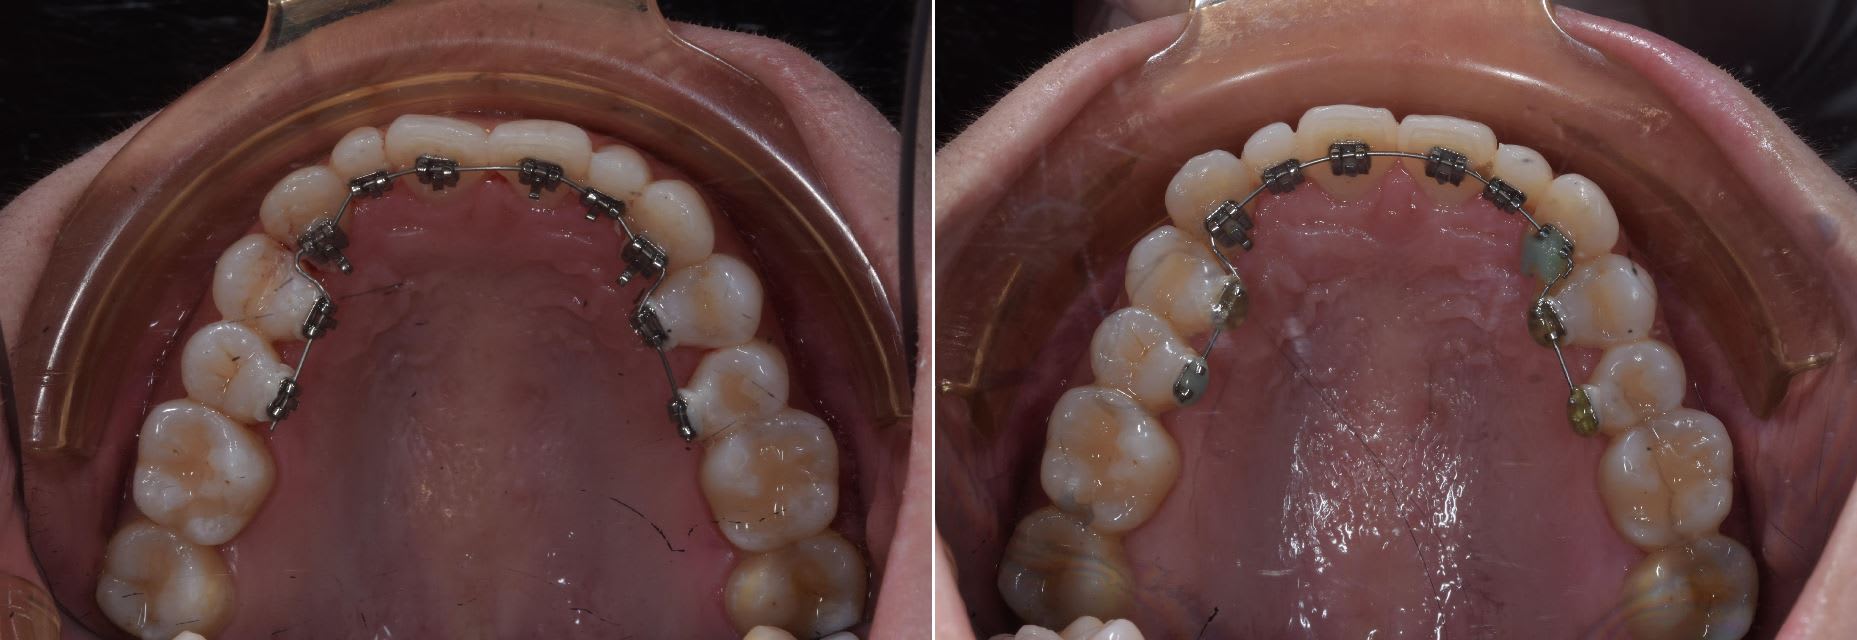

Et le suivi du patient collé il y a trois semaine. Je l'avais posté sur ce fil

https://www.eugenol.com/sujets/419256-alternative-a-invisalign-2d-et-autre?page=2#lg=1&slide=0

Grosse plainte de la patiente car les dents on fait mal, le soft flow est tombé et elle n'aime pas les cales de surocclusion.

j'ai du lui expliquer gentiment qu'en vestibulaire ça aurait était la même chose en moins confortable, des limitations au niveau de l'alimentation et une hygiène plus dure à maintenir.

Ma patiente revue une dixaine de jours après la pose du niti 18 en haut et niti 16 en bas.

Elle repart en Europe se soir avec les impression 3D et le fil préplier.

Je dois dire que pour 9 semaine de traitement pas de quoi avoir honte , et je doute que ça eu était meilleur avec invisalign